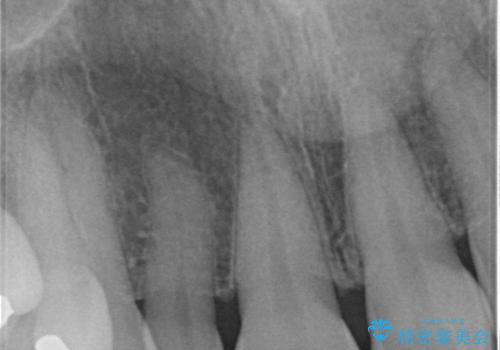

- 右上の2番目の前歯がとがった形をしていたため、セラミックで形を整えています。

下の前歯とのかみ合わせが切端咬合だったため、前歯の部分矯正も併せて行っています。(費用別途)